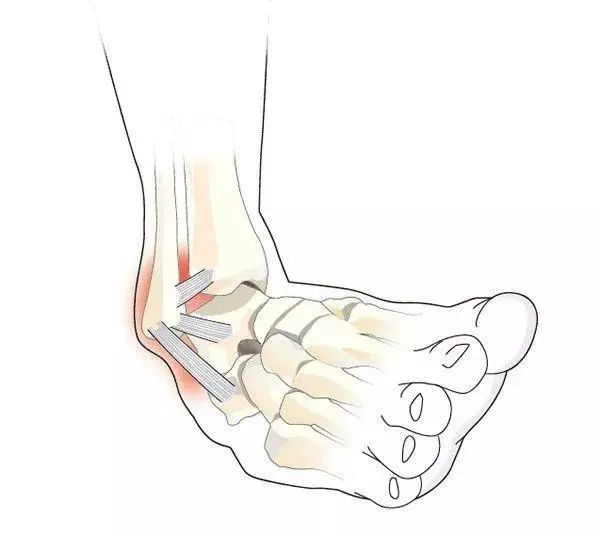

韧带是使各骨块相互连接的结缔组织索状物,附着在关节周围和内部,维持关节稳定和正常活动。

韧带拉伤是因暴力外伤导致连接两骨之间的韧带超过其耐受能力而出现的损伤。患者可有剧烈疼痛、关节及周围肿胀、关节积液、活动受限等临床表现。

韧带拉伤它是指在运动或者其他的外伤导致的情况下,引起韧带纤维的撕裂。会导致关节的稳定性丢失,以及引起局部的疼痛肿胀,活动功能受限。这种情况需要积极的进行休息,避免行走,可以受伤两天之内间断性的冷敷,受伤两天之后局部热敷,消炎镇痛药物对症治疗,不要推拿按摩,如果损害比较严重的话,还是需要进行手术治疗的。保守治疗最好需要休息3到4周的时间。